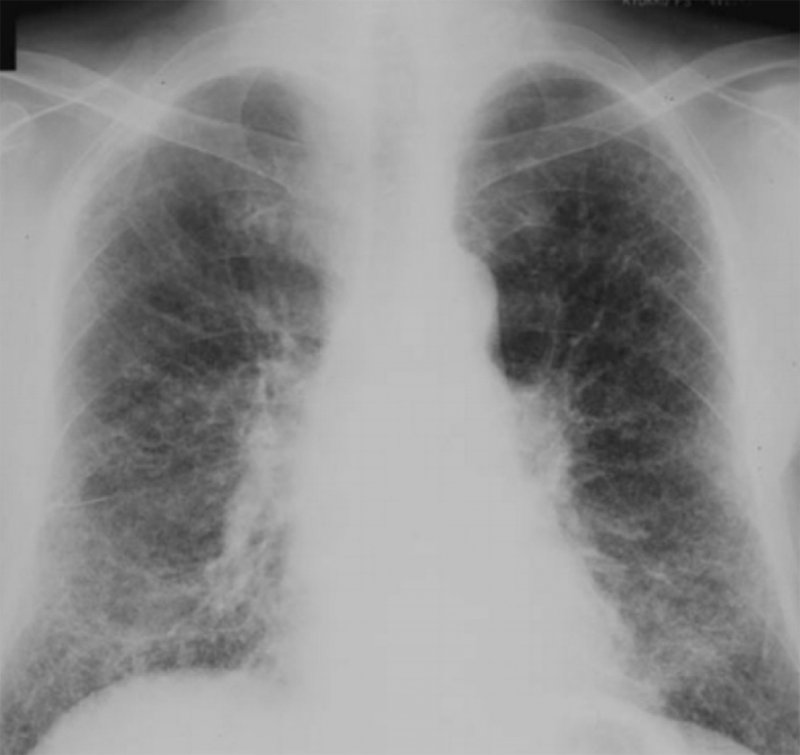

Рисунок 2. Силикоз I-II стадии. В обоих легких определяются многочисленные мелкие узелки, размером 2-3 мм. Изменения преобладают в средних отделах легочных полей

Рисунок 3. Силикоз. Увеличенный фрагмент рентгенограммы в прямой проекции – нижние отделы правого легочного поля. У больного в обоих легких определяются множественные, достаточно четко ограниченные милиарные узелки и диффузные ретикулярные изменения